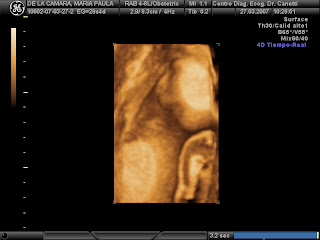

Presentando a Abril...

A ver, mirá para la cámara, Abril...